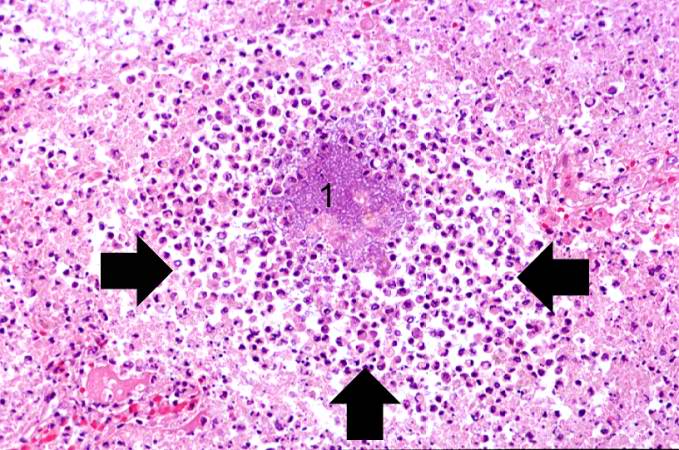

What is caseous necrosis?

This is a type of necrosis characterized by a cheese-like appearance of the affected tissue.

[Image 1] [Image 2] [Image 3]

Further notes:

It is most commonly associated with tuberculosis, where granulomas form in the lungs; the necrotic tissue is often enclosed within a granuloma, a structure formed by the immune system to wall off the infection.